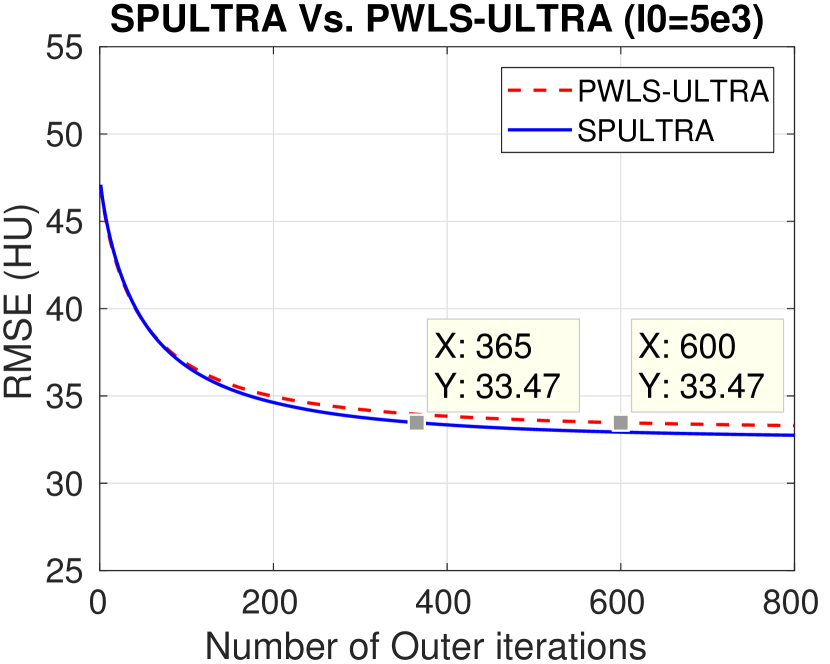

We compare the RMSE and the SSIM for SPULTRA with those for PWLS-EP and PWLS-ULTRA. Tab. II lists the two metrics for the reconstruction targeted ROI after sufficient iterations (800 iterations) for convergence of PWLS-EP, PWLS-ULTRA, and SPULTRA, for various dose levels. The results show that SPULTRA achieves significant improvements in RMSE and SSIM in low-dose situations. Notably, compared to PWLS-ULTRA, SPULTRA further decreases the RMSE by up to 1.3 HU when , and by around 3.3 HU when .

The RMSE improvement of SPULTRA over PWLS-ULTRA can be more clearly observed from Fig. 3 that shows the RMSE evolution with the number of outer iterations under different dose levels. At low-doses, SPULTRA decreases the RMSE more quickly (from the same initial value) and to much lower levels than PWLS-ULTRA. Fig. 3 shows that to achieve the same RMSE as PWLS-ULTRA at 600 outer iterations, SPULTRA takes 487, 365, 251 and 133 outer iterations under , respectively.

V-A4 Computational Costs

As discussed in Sec. III-D, SPULTRA has a similar computational cost per iteration as PWLS-ULTRA, except for computing some initializations for image update. Fig. 3 shows that the SPULTRA method requires much fewer number of outer iterations than PWLS-ULTRA to achieve the same RMSE for the reconstruction, especially at low doses.

When the dose is very low, e.g., when , SPULTRA takes only a quarter the number of outer iterations as PWLS-ULTRA to achieve the same RMSE. Thus, the total runtime to achieve a specific reconstruction quality at low doses is typically much lower for SPULTRA than for PWLS-ULTRA. When the dose is not very low, for example when , the SPULTRA and the PWLS-ULTRA methods have similar computational costs and runtimes. To achieve RMSE of 29.26 HU (see Fig. 3(a)), PWLS-ULTRA requires 600 outer iterations, while SPULTRA requires 487 584 effective outer iterations where the additional runtime is associated with initializations in each SPULTRA outer iteration.